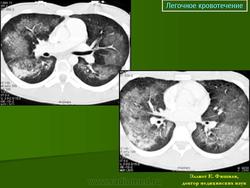

Лёгочная геморрагия.